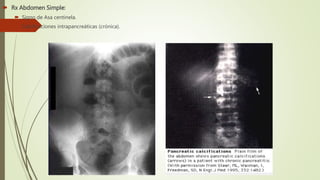

 RX SIMPLE DE ABDOMEN DE PIE: no es útil para el diagnostico, pero permite

identificar hallazgos sugestivos como: íleo, amputación de colon, imagen en

asa centinela en CSI, asa de duodeno dilatada con colección de gas, gas

retroperitoneal.

 Rx Abdomen Simple:

 Signo de Asa centinela.

 Calcificaciones intrapancreáticas (crónica).